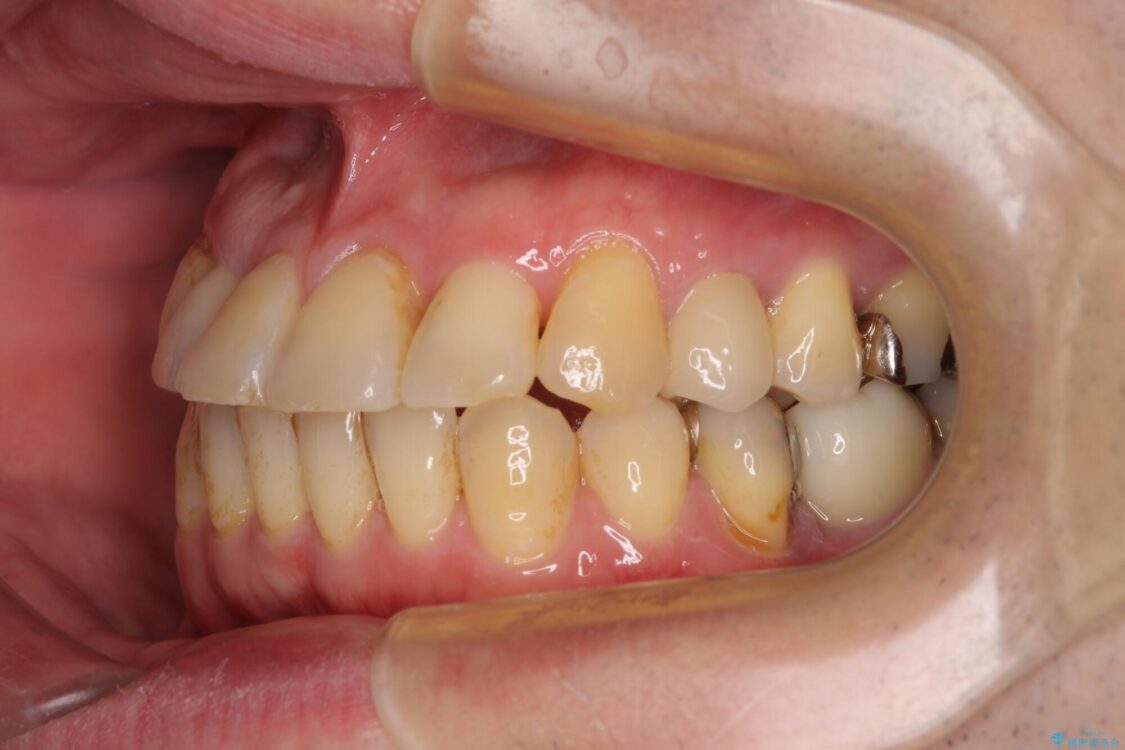

矯正治療でインプラント埋入を行い、矯正治療後に気になる前歯と合わせてオールセラミッククラウンによる補綴治療を行うこととしました。

治療後について

骨造成や歯肉移植など、治癒期間の長い処置を必要としたため治療期間は長くなりましたが、安定した咬み合わせと整った歯列となり、患者様には大変満足していただきました。

治療後

• 割れてしまった奥歯とデコボコの前歯 矯正治療とインプラント治療 治療後画像